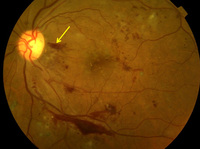

Proliferative diabetic retinopathy: nerve fibre layer haemorrhage (yellow arrow)

Courtesy of Moorfields Photographic Archive; used with permission